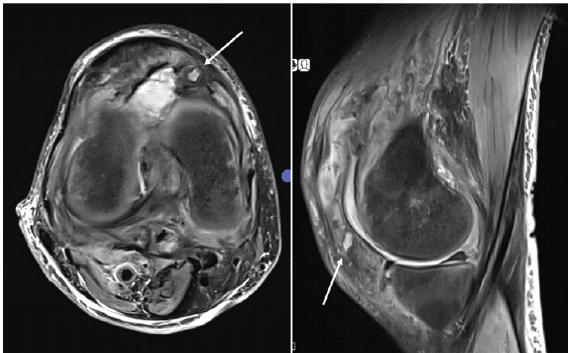

A 60-year-old male with a history of diabetes, hypertension, hypothyroidism, and coronary artery disease presented with acute painful swelling of the right knee. Clinical examination revealed diffuse swelling, tenderness over the knee joint and leg, and fullness in the popliteal fossa. Initial Doppler ultrasonography demonstrated a DVT of the right popliteal vein, and anticoagulation was initiated, leading to partial resolution of limb edema, although the knee swelling persisted. Subsequent magnetic resonance imaging (MRI) of the knee revealed a ruptured Baker’s cyst with a large joint effusion. Arthrocentesis yielded yellow, turbid synovial fluid, which cultured Staphylococcus aureus. The patient underwent arthroscopic lavage, Baker’s cyst decompression, and synovial biopsy. Histopathology and culture confirmed septic arthritis, and he was treated with intravenous culture-sensitive cephalosporin, resulting in symptomatic improvement and normalization of inflammatory markers. Three weeks later, the patient again presented with painful knee swelling. Aspiration at this stage revealed hemarthrosis, but cultures were sterile. The swelling decreased when anticoagulation was withheld, suggesting a possible anticoagulation-related bleed. However, a third episode of acute hemarthrosis occurred despite cessation of anticoagulation, raising suspicion of a vascular cause. Initial MRI of the knee demonstrated a periarticular lesion (Fig. 1), and Doppler ultrasonography suggested a vascular etiology (Fig. 2).

Figure 1: Axial and sagittal T2-weighted magnetic resonance images of the right knee showing a periarticular lesion adjacent to the joint capsule (white arrow).